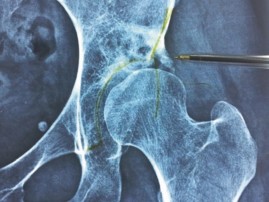

Intra-substance ossification and fracture of the ream of the acetabular roof with a cyst adjacent to the roof…